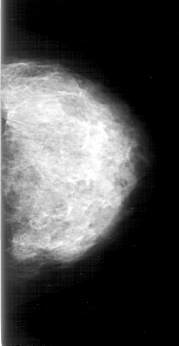

D_4192_1.RIGHT_MLO

RIGHT_MLO LINES 5971 PIXELS_PER_LINE 3346 BITS_PER_PIXEL 12 RESOLUTION 43.5 OVERLAY

FILE: D_4192_1.RIGHT_MLO.OVERLAY

TOTAL_ABNORMALITIES 1

ABNORMALITY 1

LESION_TYPE CALCIFICATION TYPE AMORPHOUS-PLEOMORPHIC DISTRIBUTION REGIONAL

ASSESSMENT 5

SUBTLETY 5

PATHOLOGY MALIGNANT